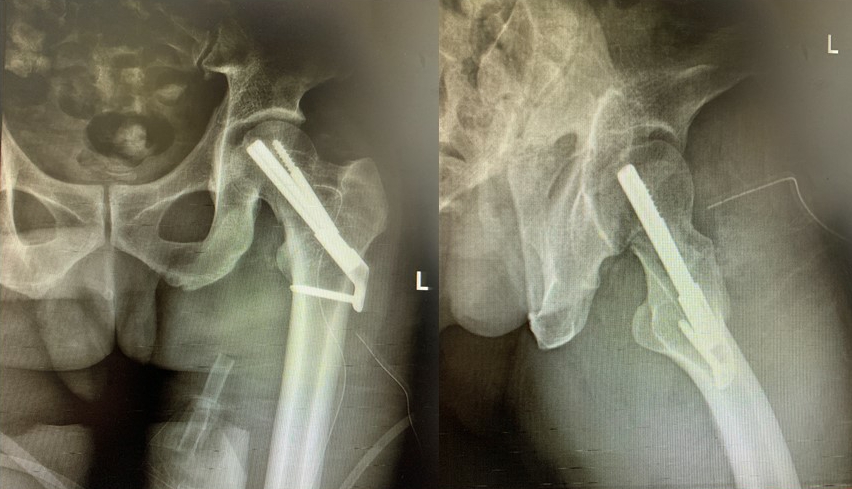

7月13日,中南大学湘雅三医院创伤骨科成功开展了省内第一例利用国际领先的股骨颈骨折内固定技术——股骨颈动力交叉钉(FNS)系统微创治疗股骨颈骨折。该技术创伤更小,稳定性更佳,利于患者恢复。

创伤骨科主任罗令带领郭强博士、李骁宁博士等创伤骨科团队成员立即开展讨论,制定了详细周密的手术计划,根据骨折类型及本人意愿,最终决定采用一种新型内固定系统——股骨颈动力交叉钉系统(FNS),力争以最小的创伤获得最坚强的固定效果和最好的预后。整个手术过程顺利,骨折闭合复位和置钉位置均十分理想,术后复查固定效果满意,患者恢复良好。